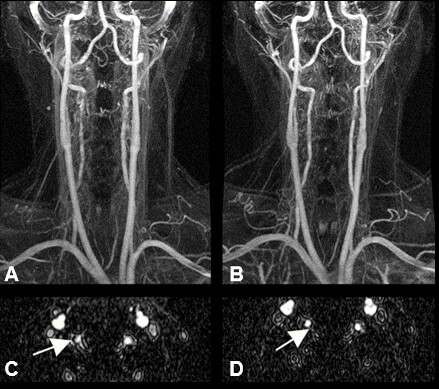

When Noise is Acceptable

Some image sequences will inherently have more noise than signal. Most are 3D images that will require post-processing to make it look “better”. An example is the 3D collection of data during vascular imaging. The MRI contrast media will provide most of the signal, and as the image data is processed and the unusable portions of the image are cut away, the image will have an appearance of less noise.

Basically speaking, it can be said that the noise is processed away, so it does not matter that it appears in the original set of data or the raw data. Here, in C and D we see the unprocessed, raw data images, which are processed into 3D model. In this instance, the raw data that is acquired during the scan is of low signal, which is acceptable to a degree. As can be seen, the processed images above in A and B look much better.